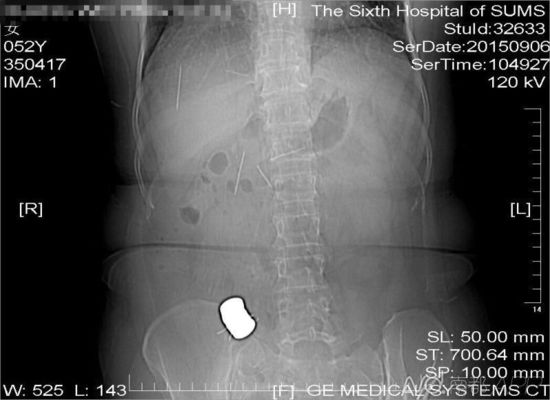

CT檢查結果中顯示,老人腹中有多個金屬異物和散落的繡花針

進行的CT檢查結果顯示,黃姨腹中有多個金屬異物和散落的繡花針。主管醫(yī)生黃俊博士介紹,這些針分別位于黃姨小腸內(nèi),部分已經(jīng)穿出小腸散播于腹腔內(nèi),還有部分金屬異物,最大的一塊上附著了數(shù)根斷針,有一根插進了胰腺,剩下的一根在脊柱附近,每枚約長4厘米。